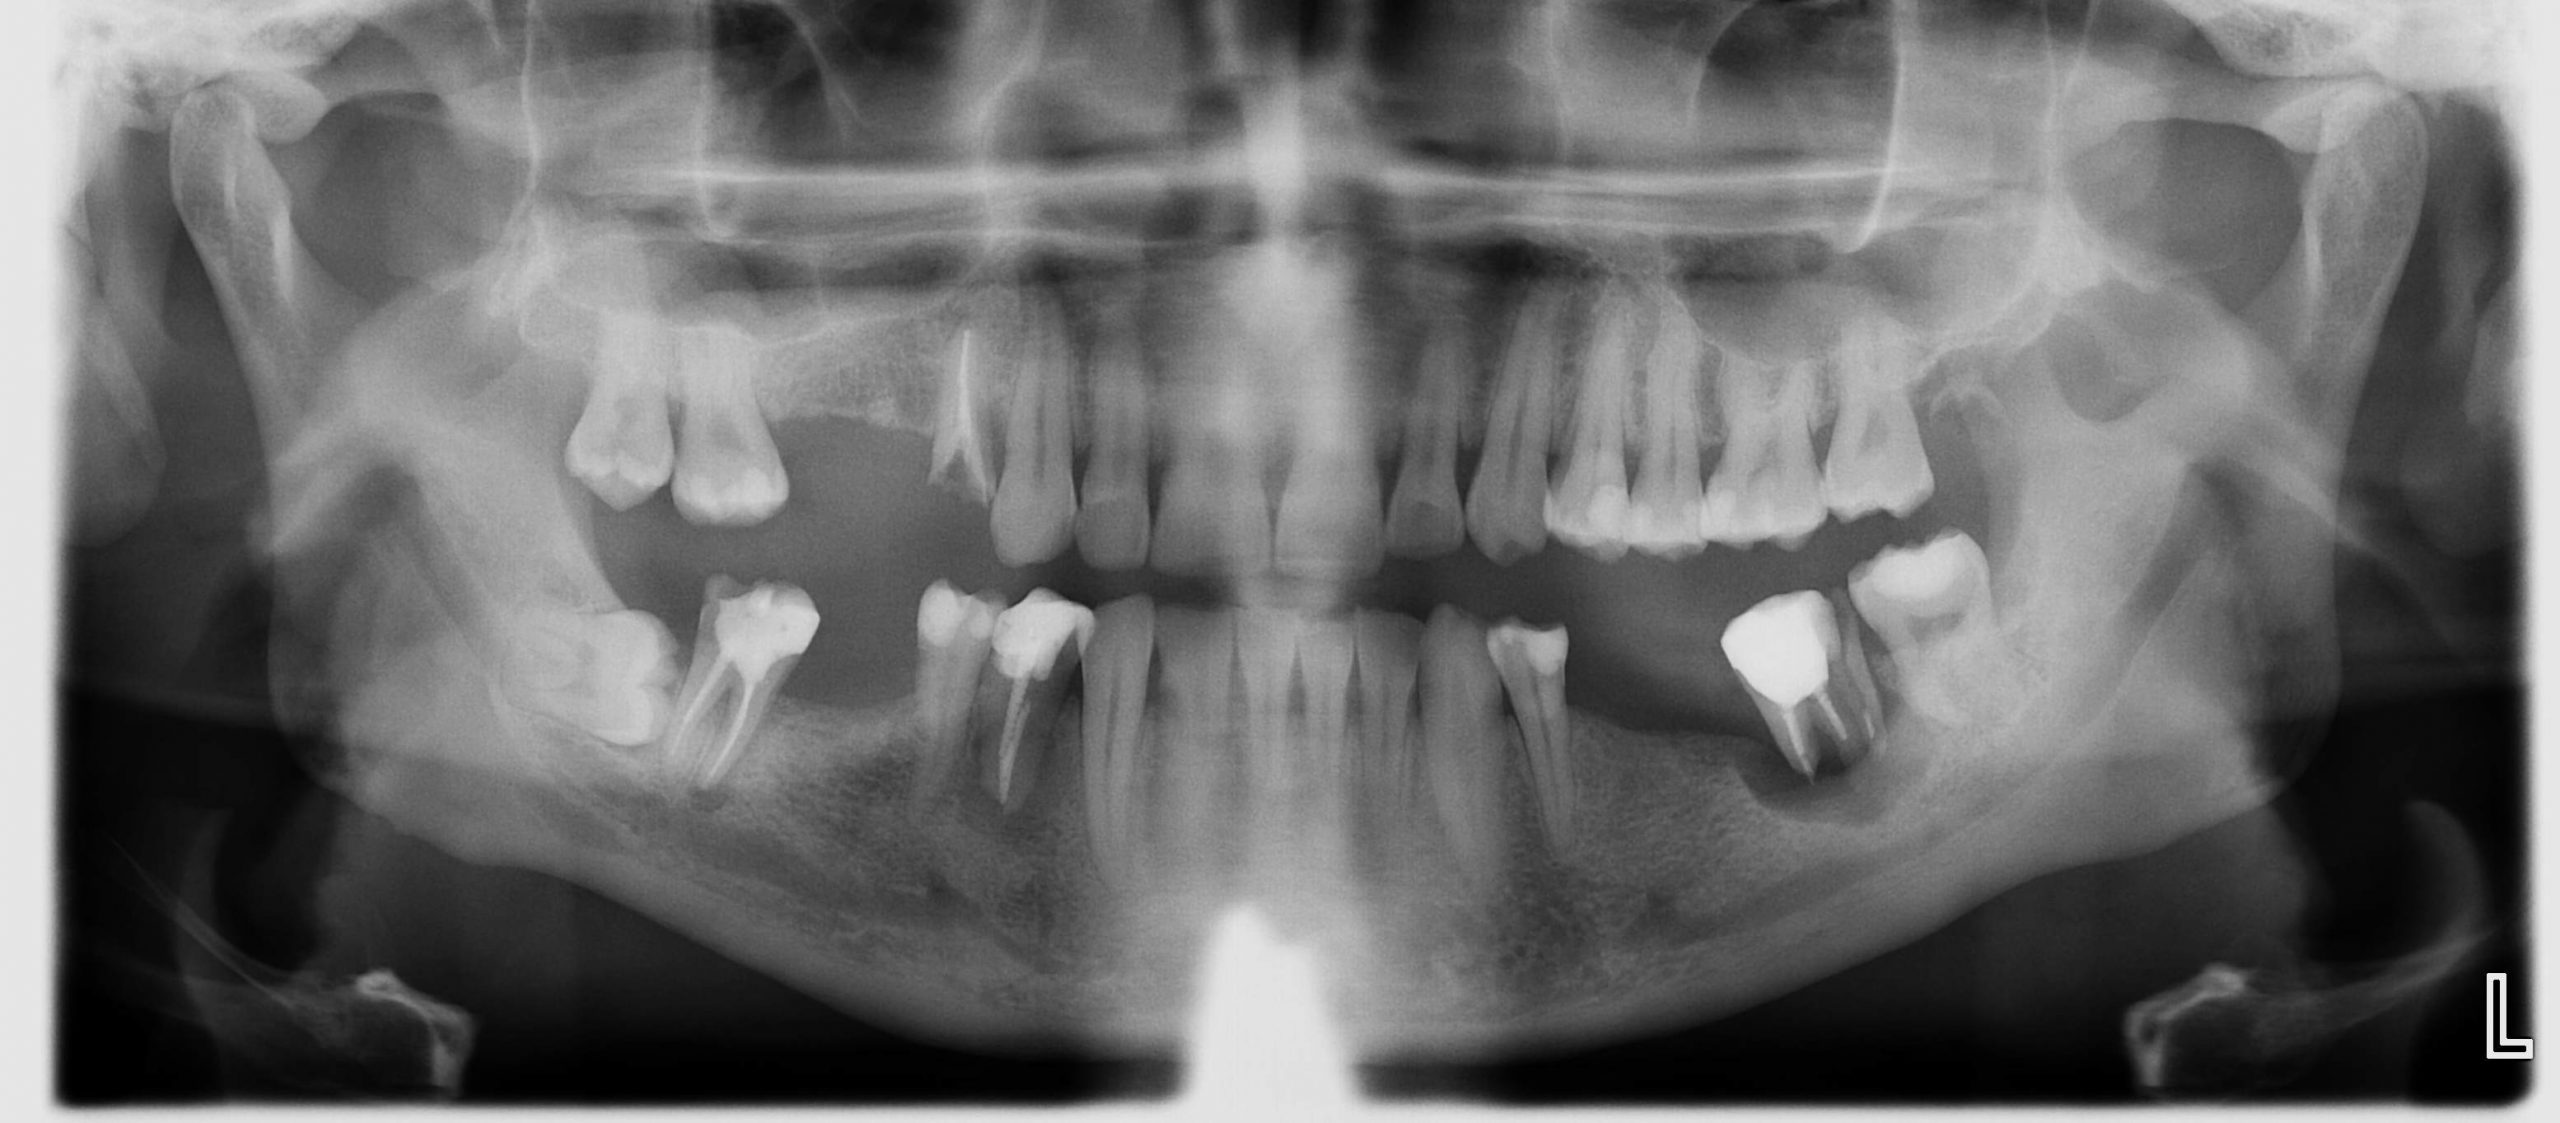

Hier ein Beispiel aus der Praxis: